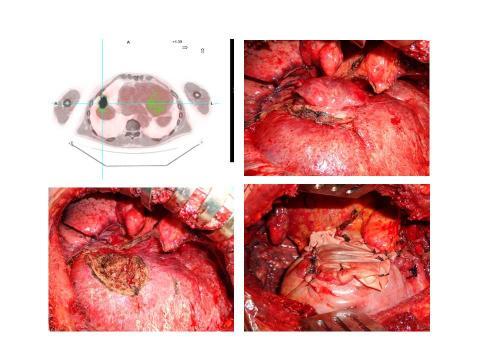

Thoracic surgical oncology

Chest wall resection and reconstruction

ECMO for pulmonary/mediastinal resections